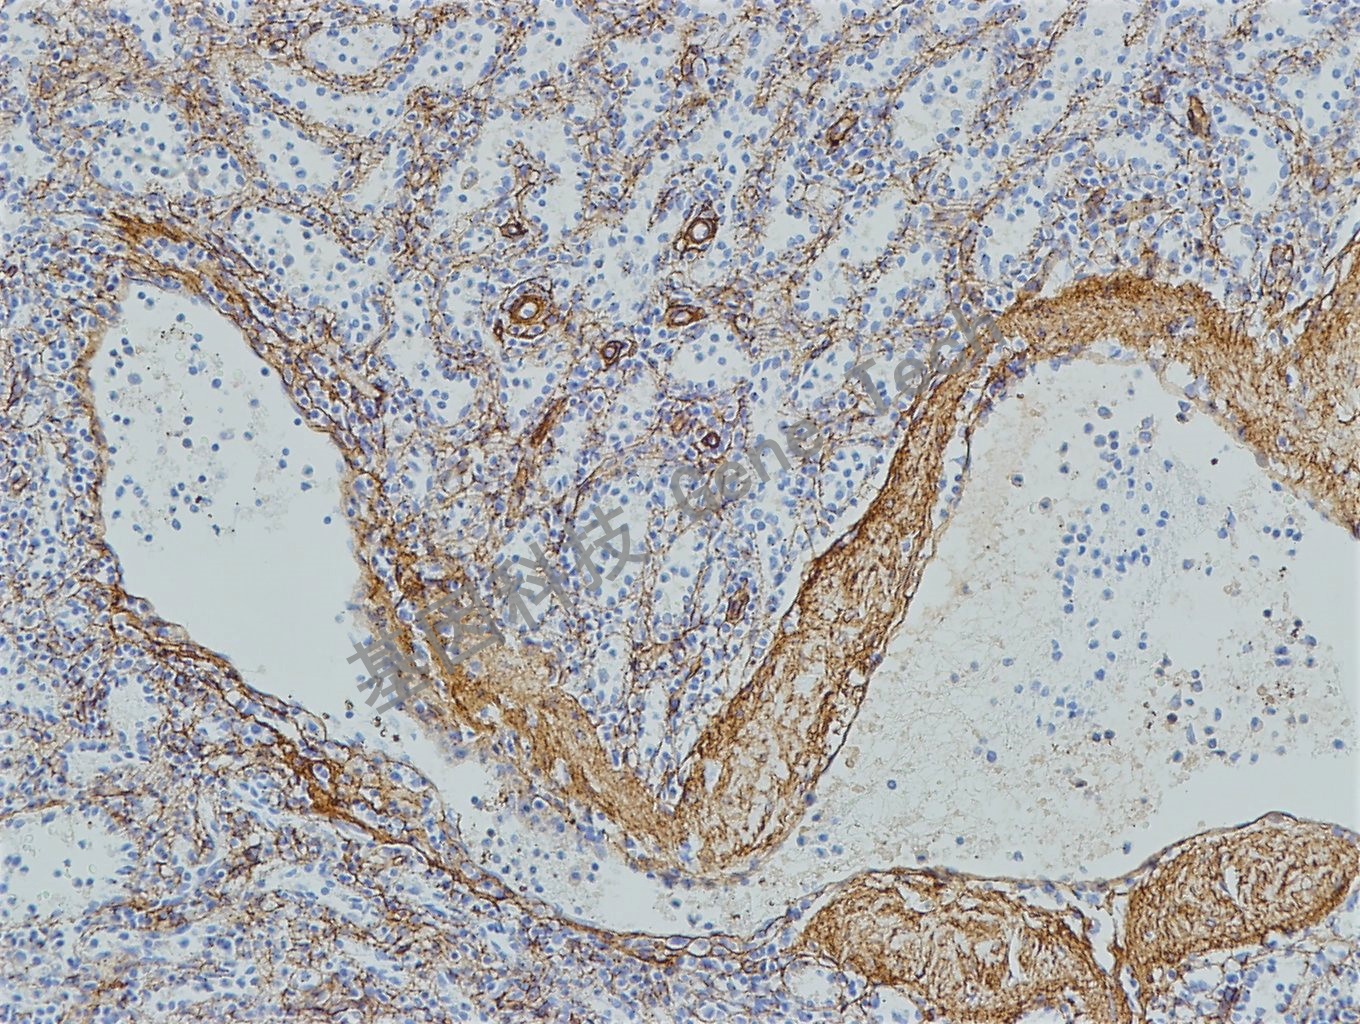

皮肤石蜡切片,用 Collagen Type IV(GT2327)染色,基底膜阳性,DAB 显色。